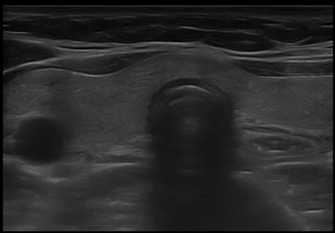

그림 1 (A)

그림 1 (B)그림 1. 주파수(frequency) 조절. 주파수를 높이면 근위부의 해상도는 좋아지지만 투과력이 저하되어 심부의 해상도가 저하되며(A), 주파수를 낮추면 투과력이 개선되어 심부의 해상도가 개선된다(B).